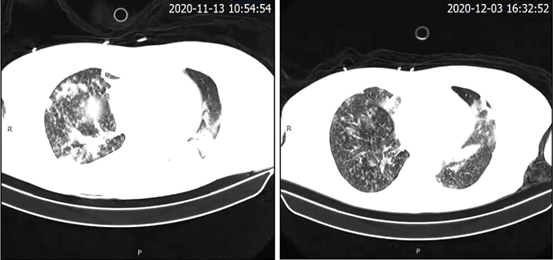

复查患者胸部CT提示右肺感染较前减轻,但左上肺感染较前加重(图2)。肺泡灌洗液病原学检查提示白假丝酵母菌,加入氟康唑抗真菌治疗,患者体温下降,感染指标好转,但临床症状未见明显减轻,痰多,纤支镜下可见气管下段通畅,黏膜光滑,隆突居中,右中间支气管、左主支气管、左上叶舌段支气管可见较多黄色黏稠分泌物堵塞管腔,左舌叶尤甚。患者常烦躁不安、乱语、谵妄,多次试图拔除气管插管,需药物镇静。

图2 患者胸部CT